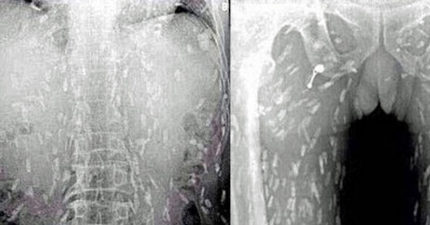

爱吃生鱼片的后果!中国男爱吃生鱼片「皮肤痒痒的」,照X光发现已经变成「虫人」了!